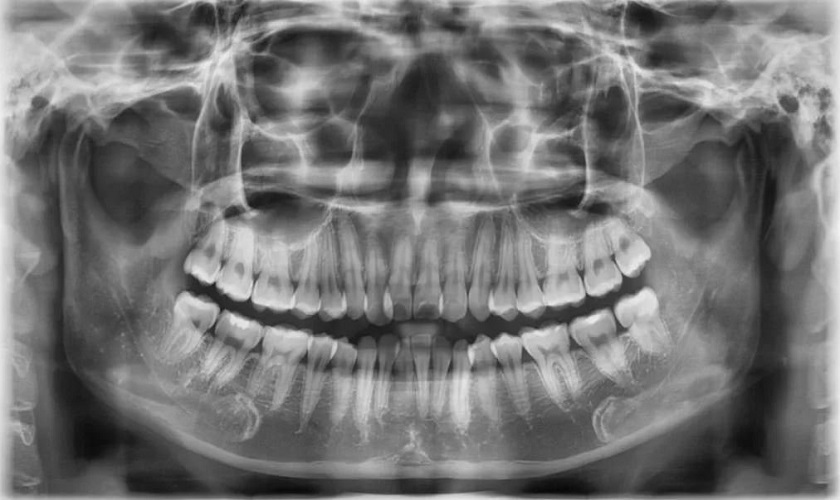

Tại Nha khoa Nhân Tâm, khách hàng sẽ được chụp X – quang để xác định vị trí, tình trạng răng trước khi nhổ. Điều này sẽ giúp bác sĩ biết được vị trí của răng có liên quan đến dây thần kinh không, nếu nhổ có gây tác động tới cấu trúc hàm hay các răng bên cạnh không, từ đó đưa ra phương án nhổ răng phù hợp. Nhờ vậy, quá trình nhổ răng số 7 sẽ được đảm bảo an toàn, không gây ra bất kì biến chứng hay nguy hiểm nào cả trong và sau tiểu phẫu.

Chụp X – quang chẩn đoán tình trạng răng trước khi nhổ